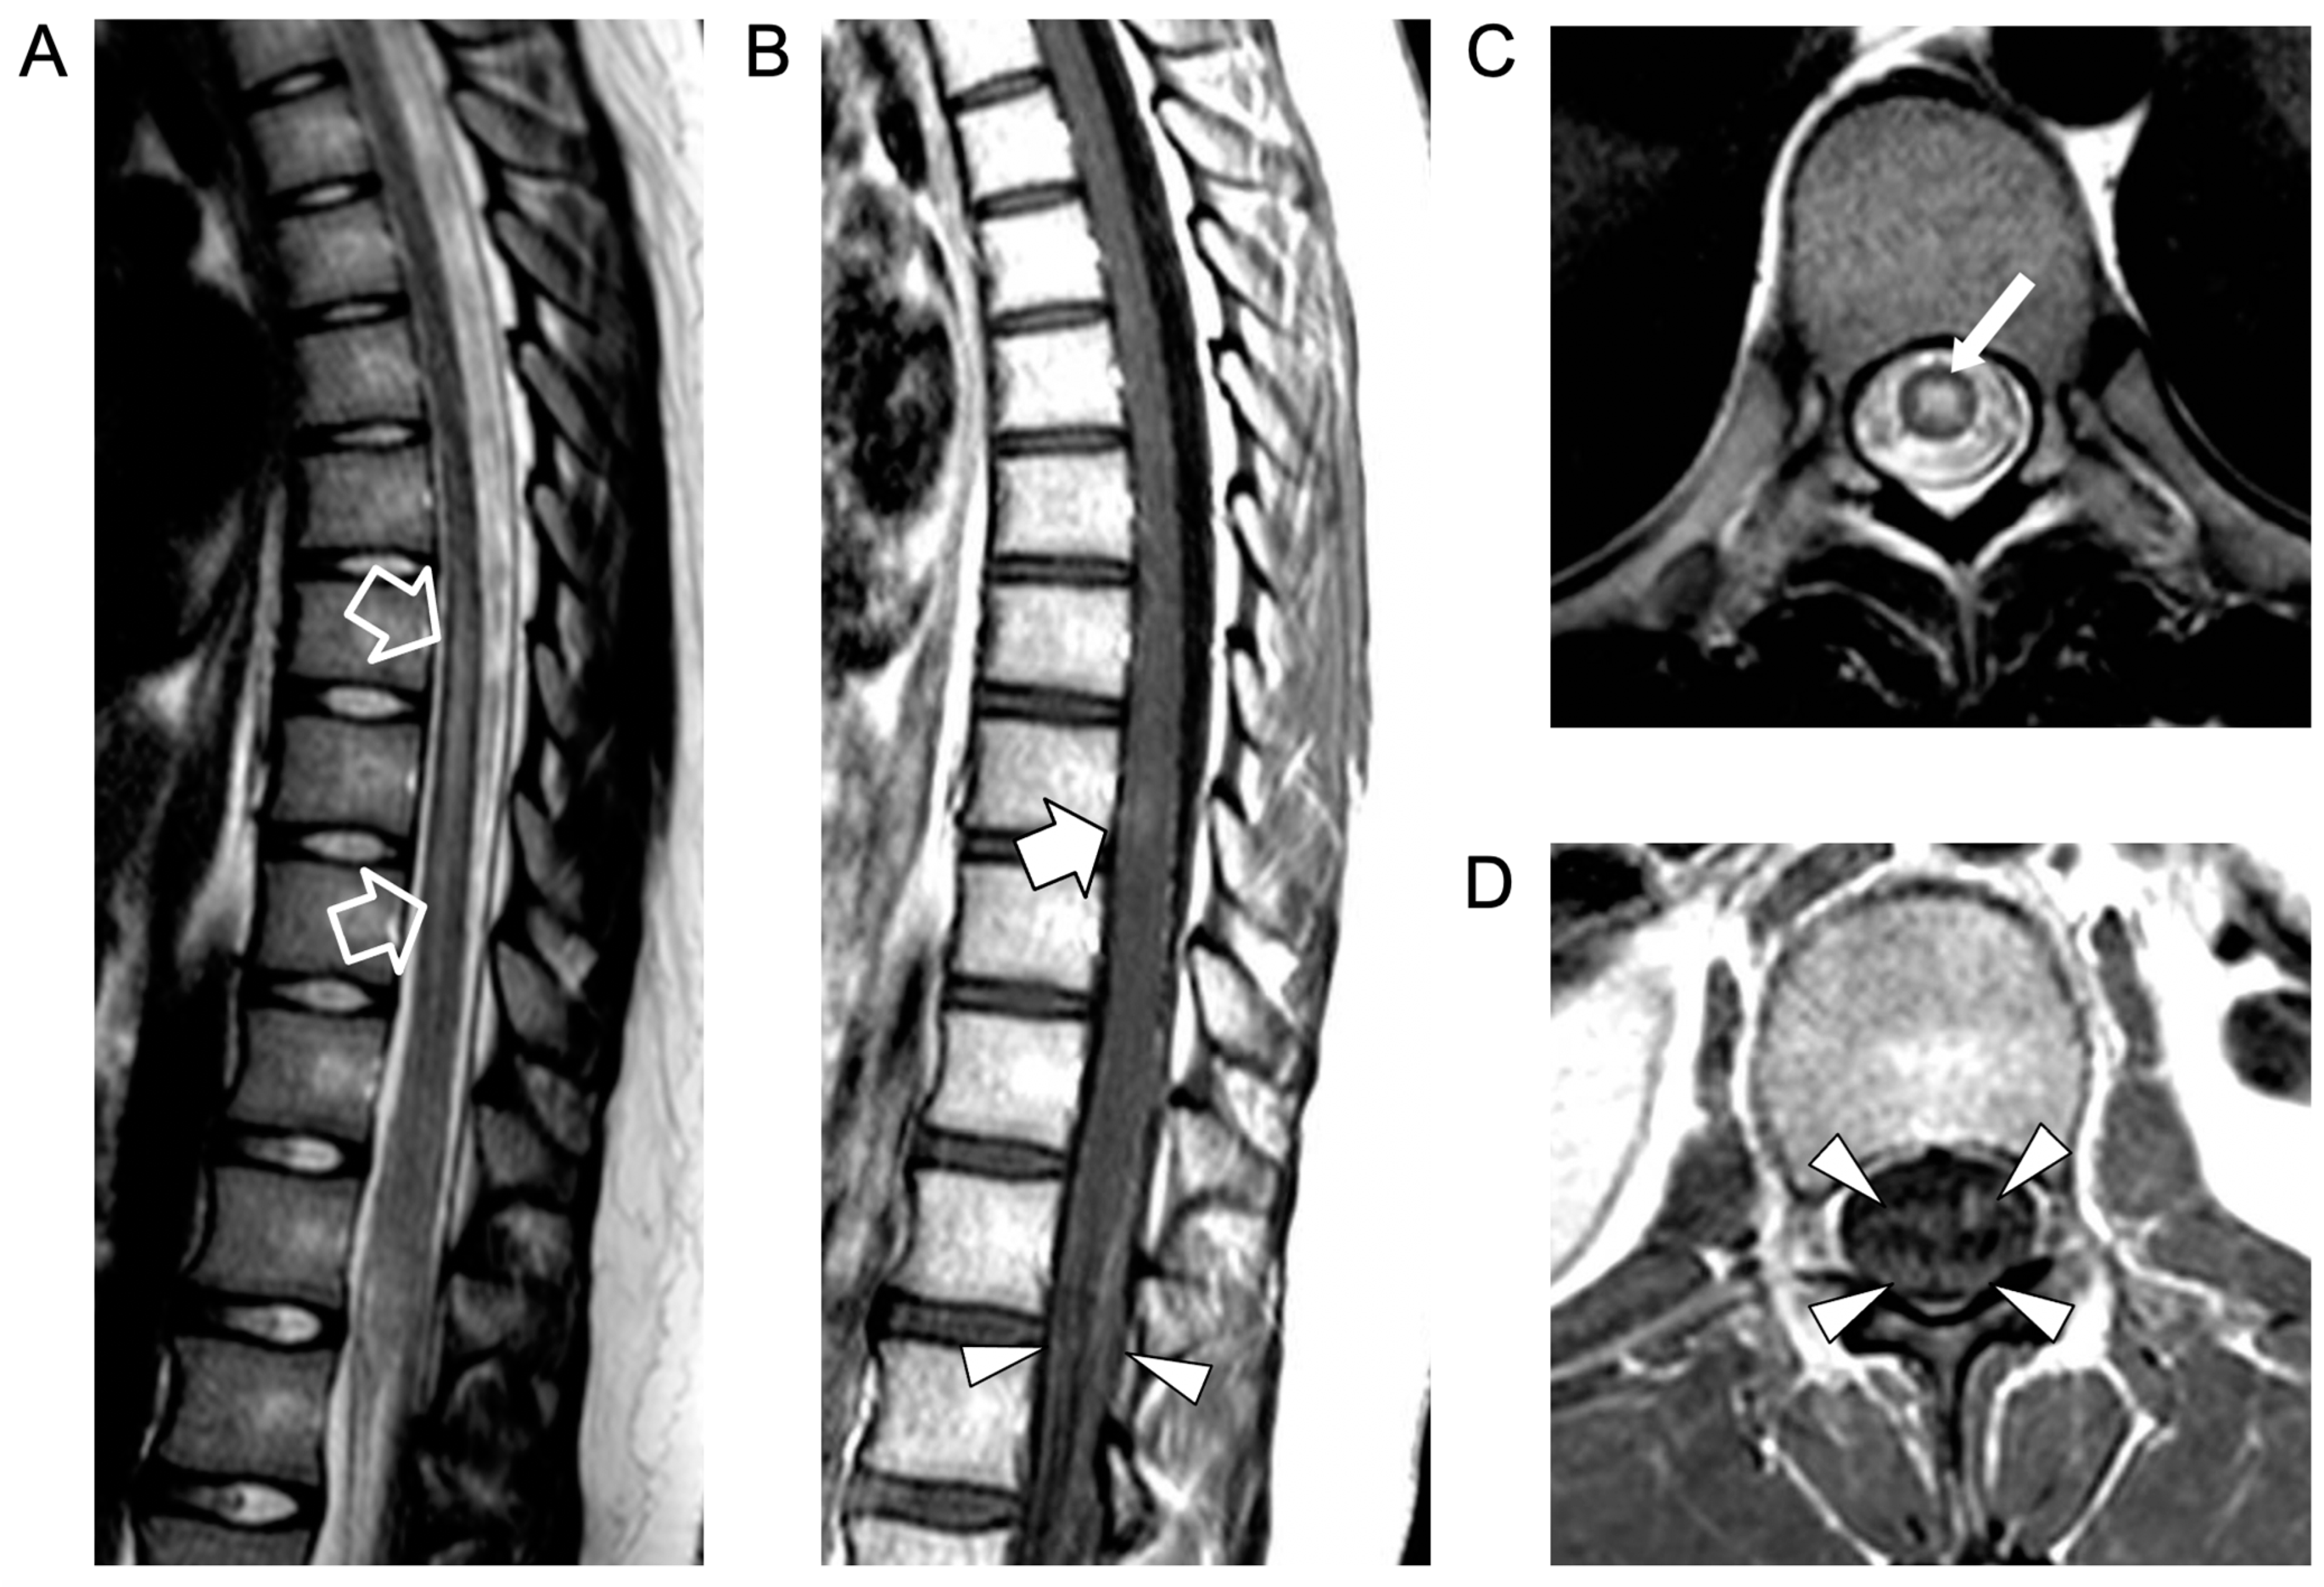

2. Case Report